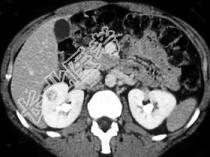

- 单项选择题根据图像,该病例最不可能的诊断为 ( )

A、嗜酸细胞瘤

B、单纯性囊肿

C、肾细胞癌

D、转移

E、以上都不是